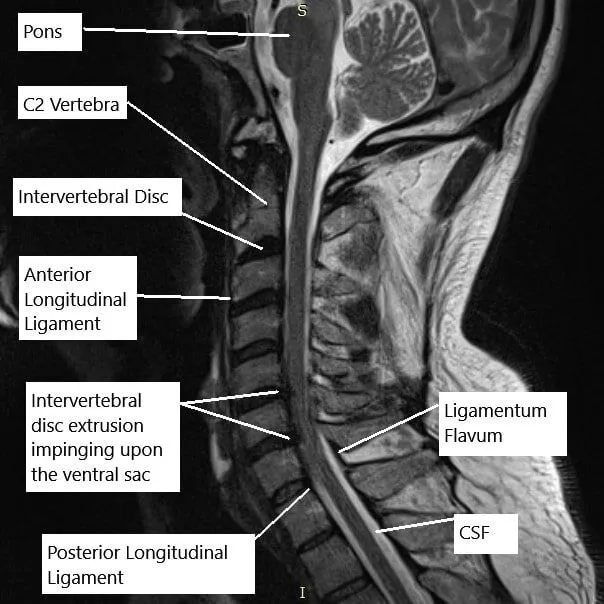

Role of MRI in Diagnosis

Magnetic Resonance Imaging (MRI) plays a pivotal role in diagnosing C5-C6 disc bulge. Unlike traditional X-rays, MRI provides detailed images of soft tissues like intervertebral discs and nerve roots. It allows healthcare professionals to assess the extent of the bulge, identify nerve compression, and rule out other potential causes of the symptoms.

A study published in the Journal of Clinical Medicine (2019) [1] highlighted the superior sensitivity of MRI in diagnosing cervical disc disorders, emphasizing its crucial role in treatment planning.

- MRI Diagram- Case Study: Cervical disc replacement in a 60-year-old female with cervical spine stenosis at C5-C6 and C6-C7 with radiculopathy and myelopathy https://www.cortho.org/case-studies/spine/cervical-disc-arthroplasty-case-study/